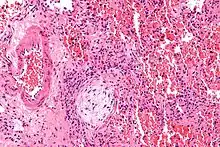

Micrograph showing a Masson body (off center left/bottom of the image – pale circular and paucicellular), as may be seen in cryptogenic organizing pneumonia. The Masson body plugs the airway. The artery associated with the obliterated airway is also seen (far left of the image). H&E stain.

Organizing pneumonia is usually preceded by some type of lung injury that causes a localized denudation or disruption in continuity of the epithelial basal laminae of the type 1 alveolar pneumocytes that line the alveoli.[9] This injury to the epithelial basal lamina results in inflammatory cells and plasma proteins leaking into the alveolar space and forming fibrin, resulting in an initial fibroblast driven intra-alveolar fibroproliferation.[9] The fibroblasts differentiate into myofibroblasts and continue to form fibrosis resulting in intra-alveolar fibroinflammatory buds (Masson's Bodies) that are characteristic of organizing pneumonia.[9] These Masson's bodies consist of inflammatory cells contained in an extracellular matrix consisting of type I collagen, fibronectin, procollagen type III, tenascin C and proteoglycans.[9] Angiogenesis , or the formation of blood vessels, occurs in the Masson's bodies and this is driven by vascular endothelial growth factor.[9] Remodeling occurs, resulting in the intra-alveolar fibroinflammatory buds (Masson's Bodies) moving into the interstitial space and forming collagen globules that are then covered by type 1 alveolar epithelial cells with well developed basement membranes. These type 1 alveolar epithelial cells (pneumocytes) then proliferate, restoring the continuity and function of the alveolar unit.[9] This process is in contrast to the histopathologic changes seen in usual interstitial pneumonia where extensive fibrosis and inflammation occur leading to fibroblastic foci to form in the alveolar spaces resulting in obliteration of the alveolar space, scarring and significant damage to lung architecture (the alveoli).[9]

Biopsy findings in patients with organizing pneumonia consist of loose connective tissue plugs involving the alveoli, alveolar ducts and bronchioles. The loose connective tissue plugs occupying the alveolar spaces often connect to other connective tissue plugs in nearby alveoli via the pores of Kohn creating a characteristic butterfly pattern on histology.[9] There is usually minimal to no interstitial inflammatory changes in biopsies of organizing pneumonia.[9]

Histologically, cryptogenic organizing pneumonia is characterized by the presence of polypoid plugs of loose organizing connective tissue (Masson bodies) within alveolar ducts, alveoli, and bronchioles.